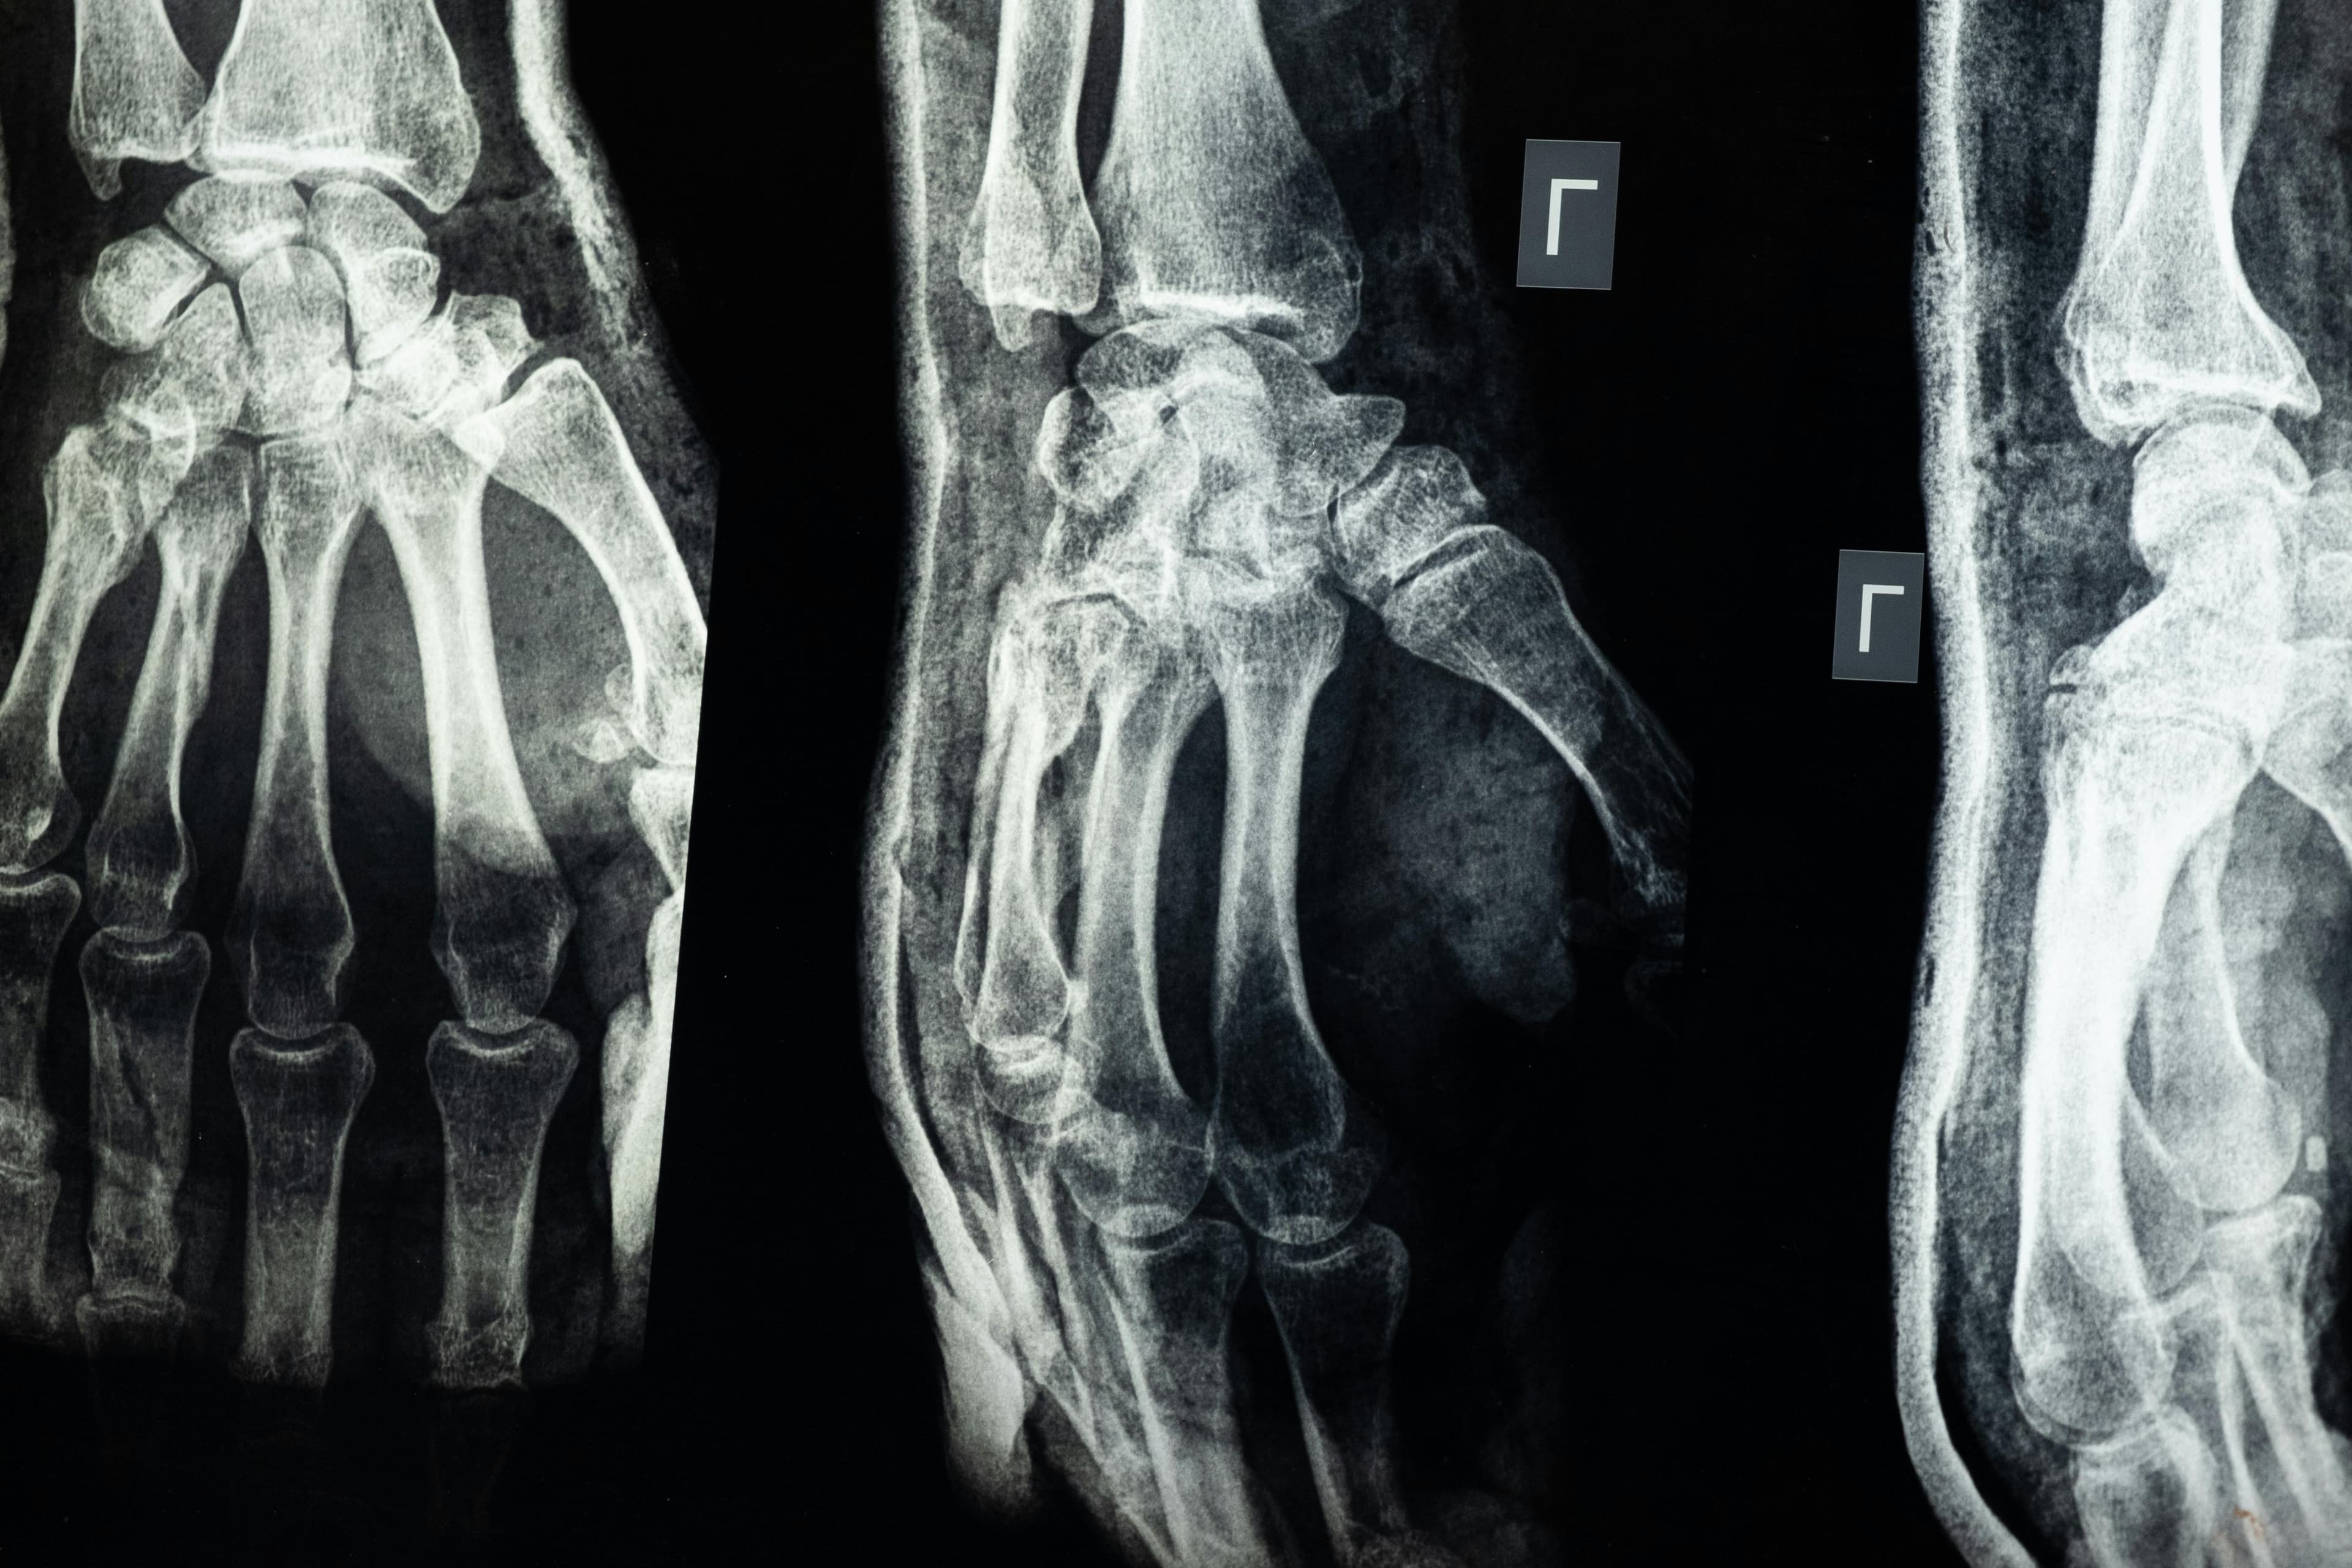

The BSc (Hons) Diagnostic Radiography and Imaging at the University of Hertfordshire offers a cutting-edge education that combines health science, patient care, and advanced imaging technology. Radiographers are vital members of the healthcare team, working closely with doctors to produce images (X-rays, CT scans, MRI, etc.) for diagnosing and treating illness. At Herts, you will benefit from outstanding facilities, including dedicated imaging labs with a fully operational CT scanner and X-ray suites, as well as virtual reality simulation software that lets you practice safely before clinical placements. In fact, Herts radiography students use the latest equipment (including ultrasound machines, a simulated operating theatre with imaging systems, and a mock ward with mobile X-ray) to build hands-on skills. The teaching team consists of highly qualified radiographers registered with the HCPC, many of whom still practice clinically – so your learning stays up-to-date with real-world innovations. This three-year degree emphasizes patient-centered care, communication skills, and evidence-based practice, ensuring you graduate as a competent, compassionate imaging professional.

One unique selling point is the programme’s strong reputation: radiography courses at Herts are ranked 9th in the UK for health professions (Guardian University Guide 2026). UK-trained radiographers are globally recognized as among the best in the field, so a Herts degree will open doors worldwide. The curriculum covers anatomy, physiology, and pathology alongside mastery of imaging modalities, from general radiography to specialized techniques. You will also learn about research methods and innovative practices, preparing you to adapt in a fast-evolving profession.

Career opportunities for radiography graduates are outstanding. Once you qualify and register with the Health and Care Professions Council (HCPC) and the Society and College of Radiographers (SCoR), you can practice as a diagnostic radiographer in a range of settings. Many graduates work in hospitals (in departments such as X-ray, CT, MRI, or ultrasound) or private imaging centers. The skill set is highly transferable internationally – UK-trained radiographers enjoy exciting global career opportunities because of their excellent reputation. In the UK, radiographers often start in the NHS, which provides a clear grading structure for advancement. With experience, you can specialize further in areas like ultrasonography, computed tomography (CT), magnetic resonance imaging (MRI), or even move into radiation therapy, research, or education. Some radiographers pursue postgraduate study to become reporting specialists or consultant practitioners.